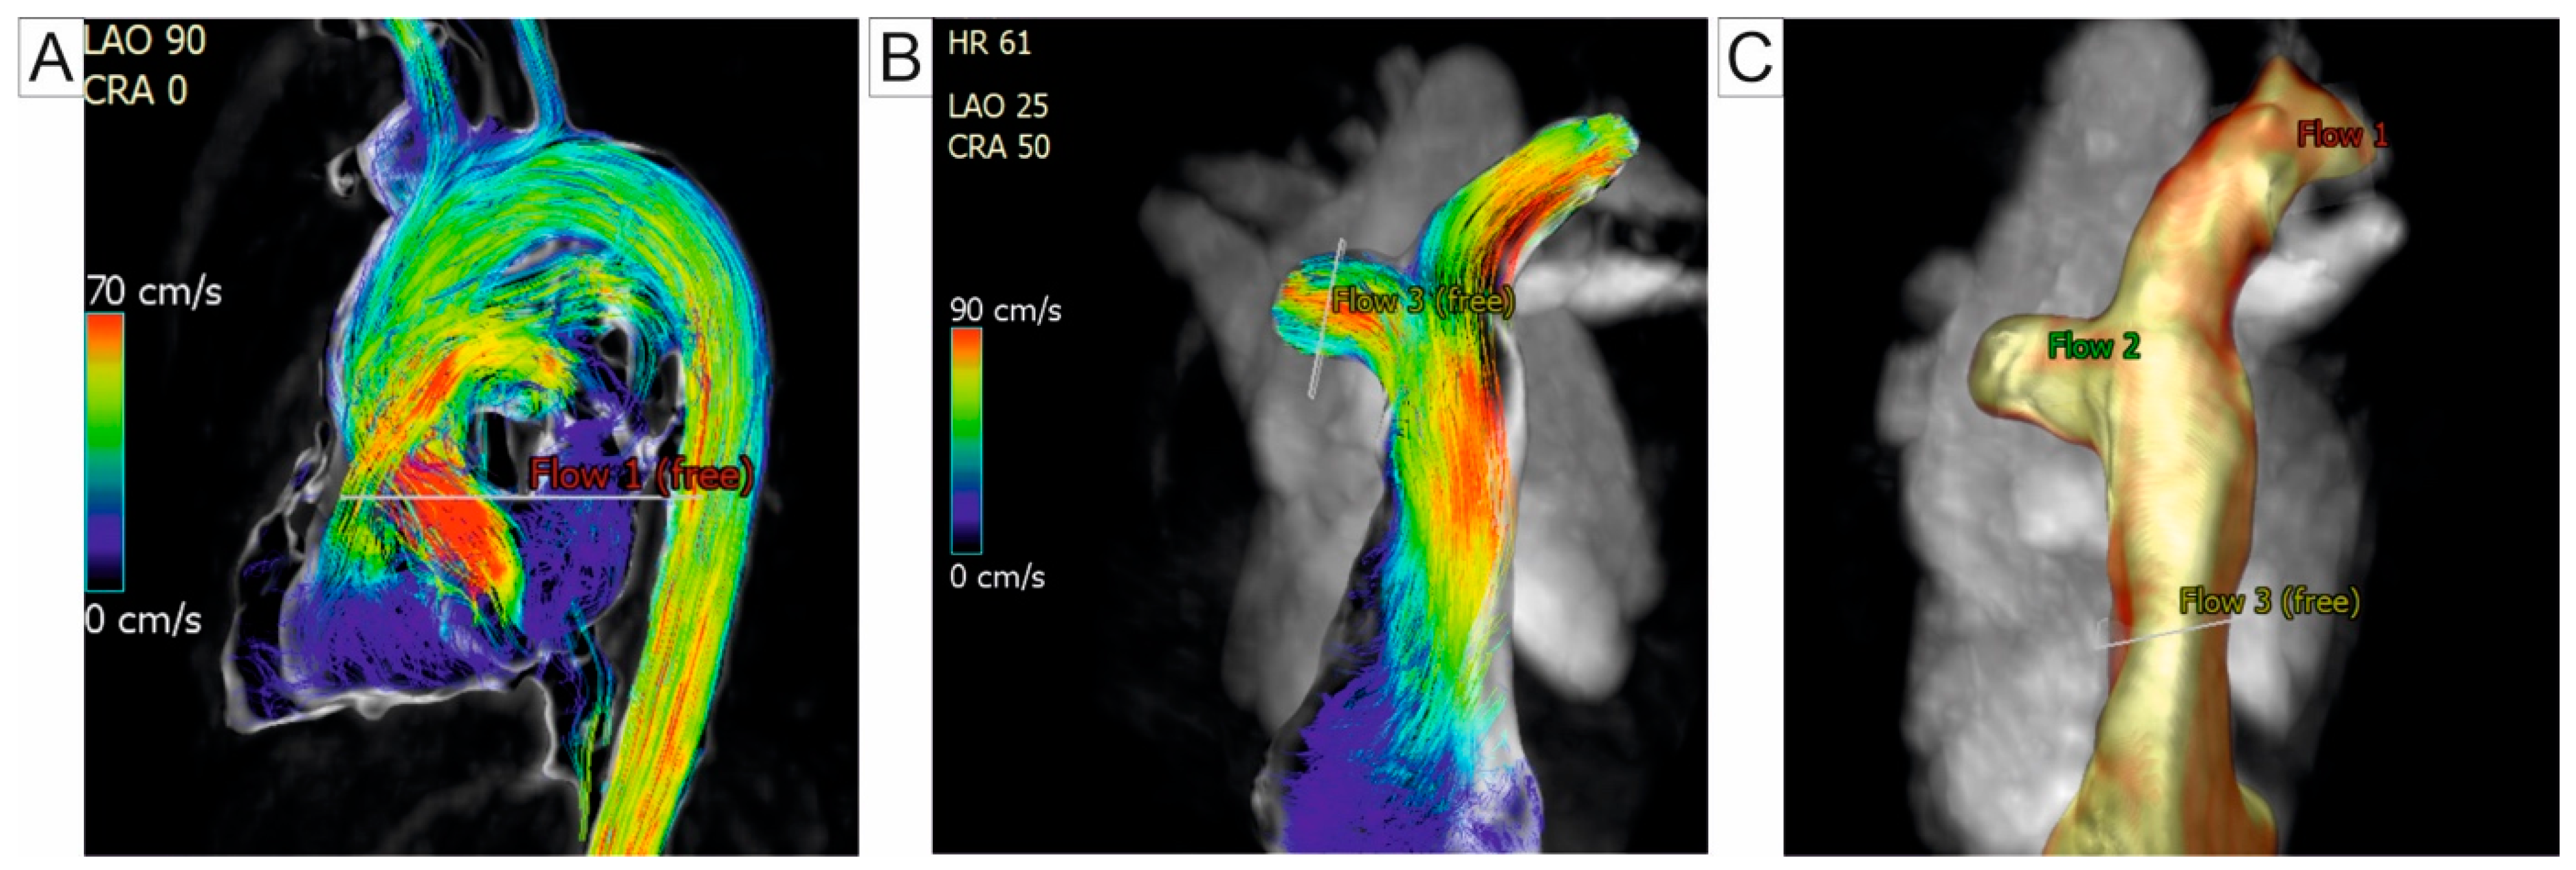

CMR is the gold standard for evaluating the right heart function [35,36], a critical determinant of prognosis in PH patients [37]. The SSFP sequence is commonly used for acquiring high-resolution volumetric datasets of the RV due to its superior blood-tissue contrast. RV volumes, mass, and function can be quantified with high intra- and inter-observer consistency and excellent reproducibility across different studies. CMR effectively detects an elevated RV end-diastolic volume, RV dilation, reduced ejection fraction, and RV hypertrophy, which are characteristic of PH [38,39]. Cine-CMR illustrates RV morphological changes, including the flattening and bowing of the interventricular septum (IVS) toward the left ventricle during the cardiac cycle. The degree of IVS curvature correlates with PAPs [40,41]. The RV end-systolic remodeling index (RVESRI), derived from CMR, is calculated as the ratio of RV free wall length to septal height at end-systole. RVESRI is strongly associated with RV remodeling and dysfunction, and an elevated RVESRI correlates with increased PA pressure and afterload. Zhang et al. reported that a RVESRI value greater than 1.35 has excellent diagnostic performance, with a sensitivity and specificity of 97.83% and 83.33%, respectively, for predicting PAPm exceeding 25 mmHg, in patients with chronic thromboembolic pulmonary hypertension (CTEPH) [42]. CMR used for RV-PA evaluation can be seen in Figure 2.

In PH, blood flow is typically irregular and turbulent, with disrupted circular patterns. Using the 4D-flow CMR, the visualization of vortex emergence within the PA vasculature is possible, serving as a valuable marker for identifying overt PH. CMR-based measurement of vortical blood flow duration in the PA trunk have been shown to accuratly estimate PAPm in resting states, enabling the non-invasive detection of PH, as suggested by Reiter et al. [63,64]. Their findings indicate that the vortical flow begins to emerge when PAPm exceeds 16 mmHg, with the duration of the vortex increasing proportionally to PAPm [63]. To differentiate the patients with PH from healthy subjects, Schafer et al. quantify helicity and vorticity in the PA. The authors found that helicity significantly decreased in the main pulmonary artery (MPA) and RPA, whereas vorticity decreased only in the RPA. Notably, these parameters showed no significant variability between the different PH subgroups. Among these markers, total helicity emerged as the non-invasive marker with the highest diagnostic precision [65]. Ramos et al. demonstrated that assessing the CMR-derived vortex duration offers superior diagnostic accuracy for tracking the PA pressure compared to the transtricuspidian gradient measurement obtained via a Doppler echocardiography [66]. Another approach to the quantifying vortex flow involves evaluating backward flow components, such as duration, volume flow rate, and cross-sectional area. Kamada et al. evaluated patients with PH due to CTEPH and concluded that these indicators are reliable for evaluating therapeutic outcomes, particularly after a balloon pulmonary angioplasty [67]. Figure 4 illustrates the PH assessment using 4D-flow CMR.

Figure 2. Cardiac magnetic resonance parameters for the assessment of the right ventricle and pulmonary artery: (A) Cine-CMR 4-chamber view showing dilated right heart chambers. (B) T1-weighted double inversion-recovery black-blood turbo spin-echo images in patient with PH, demonstrating dilatation of the PA with pulmonary flow artifact in the distal right PA (arrow). (C) Short-axis CMR image illustrating RV planimetry, involving manual tracing of myocardial boundaries: the epicardial border is marked in green, and the endocardial border is marked in red, measured in end-diastole. Abbreviations: RV, right ventricle; CMR, cardiac magnetic resonance; PA, pulmonary artery; PH, pulmonary hypertension.